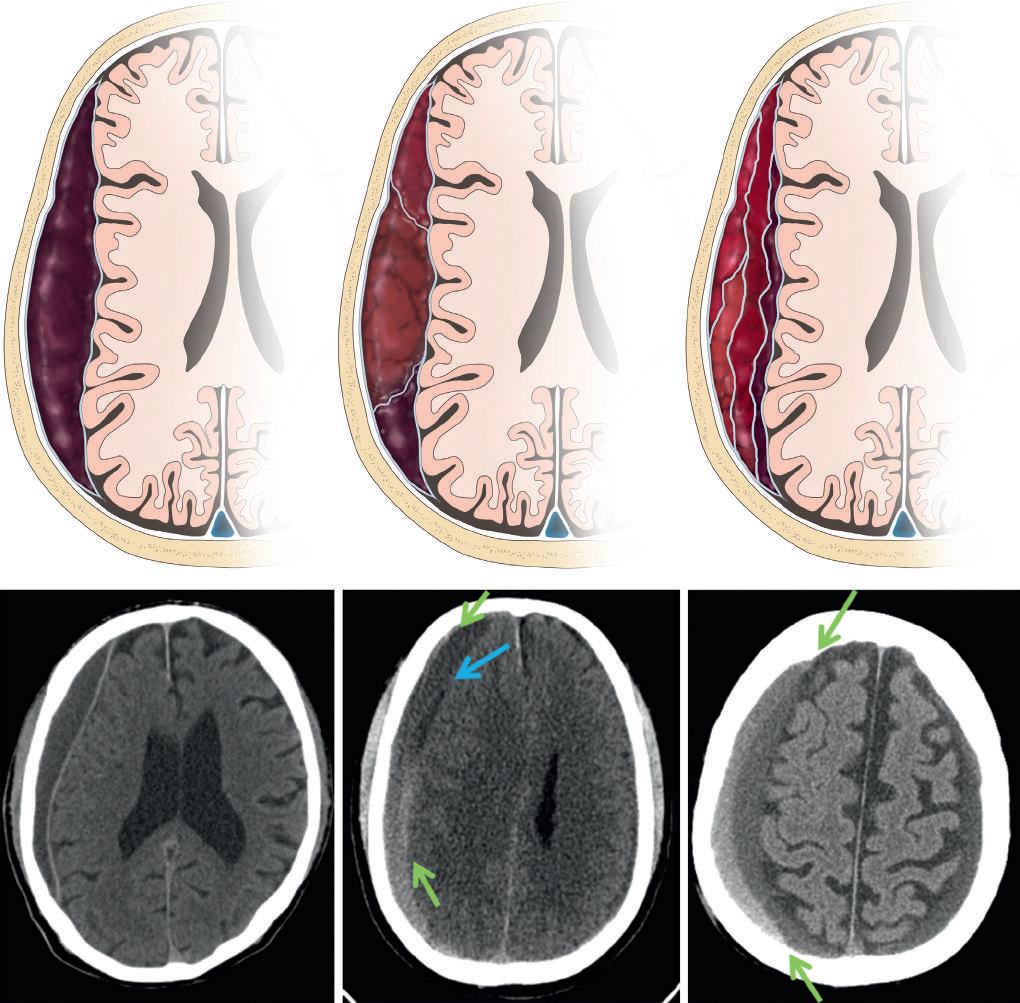

Figure 2.8. Classic descriptions of acute, subacute, and chronic subdural hematoma density. A left tentorial hyperdense subdural hematoma is evident on an axial computed tomography image a few hours after head trauma (A, white arrow). At 2.5 weeks, heterogeneously isodense blood products are evident (B, white arrow). By 4 weeks, the hematoma is entirely hypodense as compared with the brain parenchyma (C, white arrow).